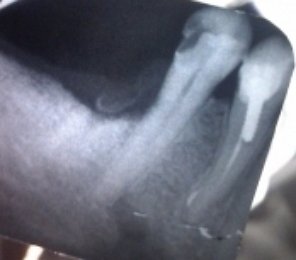

На верхней челюсти справа в районе зуба 6 образовалась небольшая припухлость, которая видна только со стороны щеки, при постукивании на сам зуб отдает болью, десна вокруг зуба не красная и не припухлая, воспаленной не выглядит, зуб залеченный.

Сделали снимок, врач, делавший снимок, направляет на удаление зуба по результатам снимка.

Возможно ли лечение этого зуба?